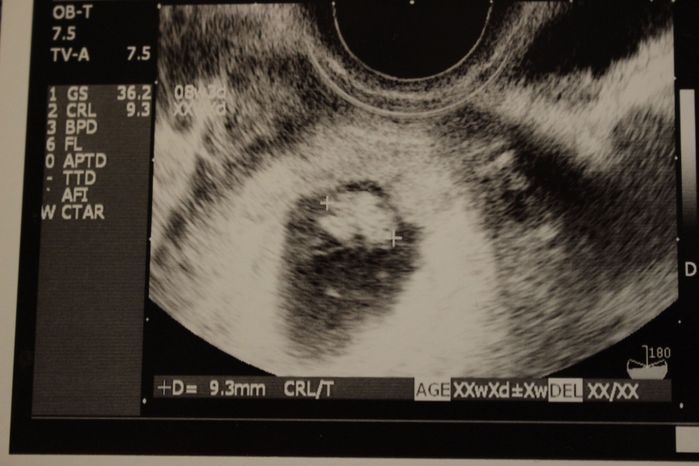

妊娠7週目のエコー写真

2週に一度の健診が待ち遠しくてたまらなかった頃です。心拍の確認と、胎芽の横に卵黄嚢という丸い輪があり、「赤ちゃんのお弁当よ」という医師の説明に生命の神秘を感じていました。出産予定日が来夏と決まり、妊娠届出書をもらって母子手帳をもらいに行きました。